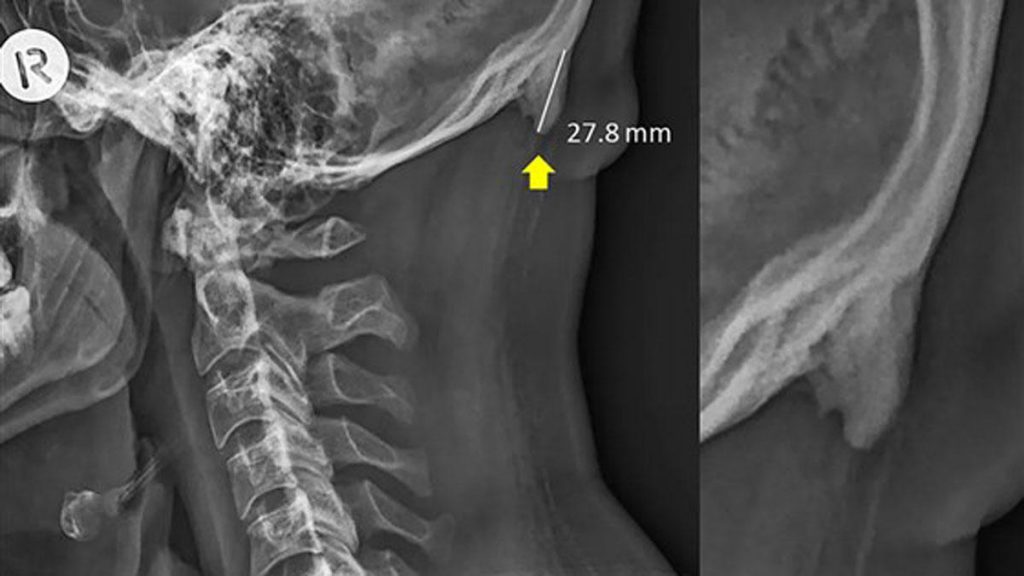

El estudio, que se publicó el año pasado en la revista Scientific Reports, encontró que las personas más jóvenes tenían crecimientos más grandes.

La mayoría de los espolones óseos en la base del cráneo no causan dolor y no requieren tratamiento, pero pueden convertirse en un problema si alcanzan cierto tamaño.